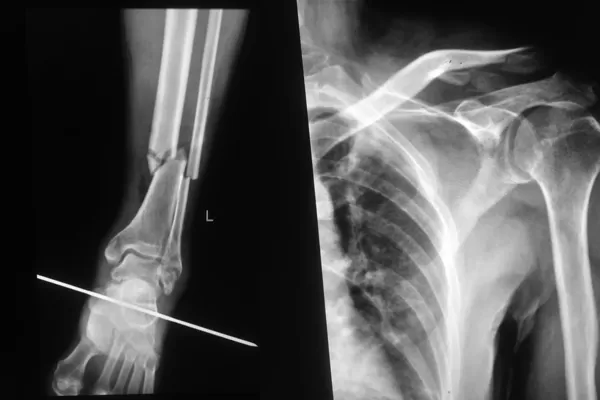

DR检查,被诊断为“左腓骨中下段粉碎性骨折、左内踝骨折、左外踝骨折、左锁骨远端粉碎性骨折”

入院不久后,在宜宾民心创伤骨科医院骨科主任的带领下,医疗团队先后为王某成功实施了“左腓骨、左内踝切开复位内固定术+左锁骨切开复位内固定术”